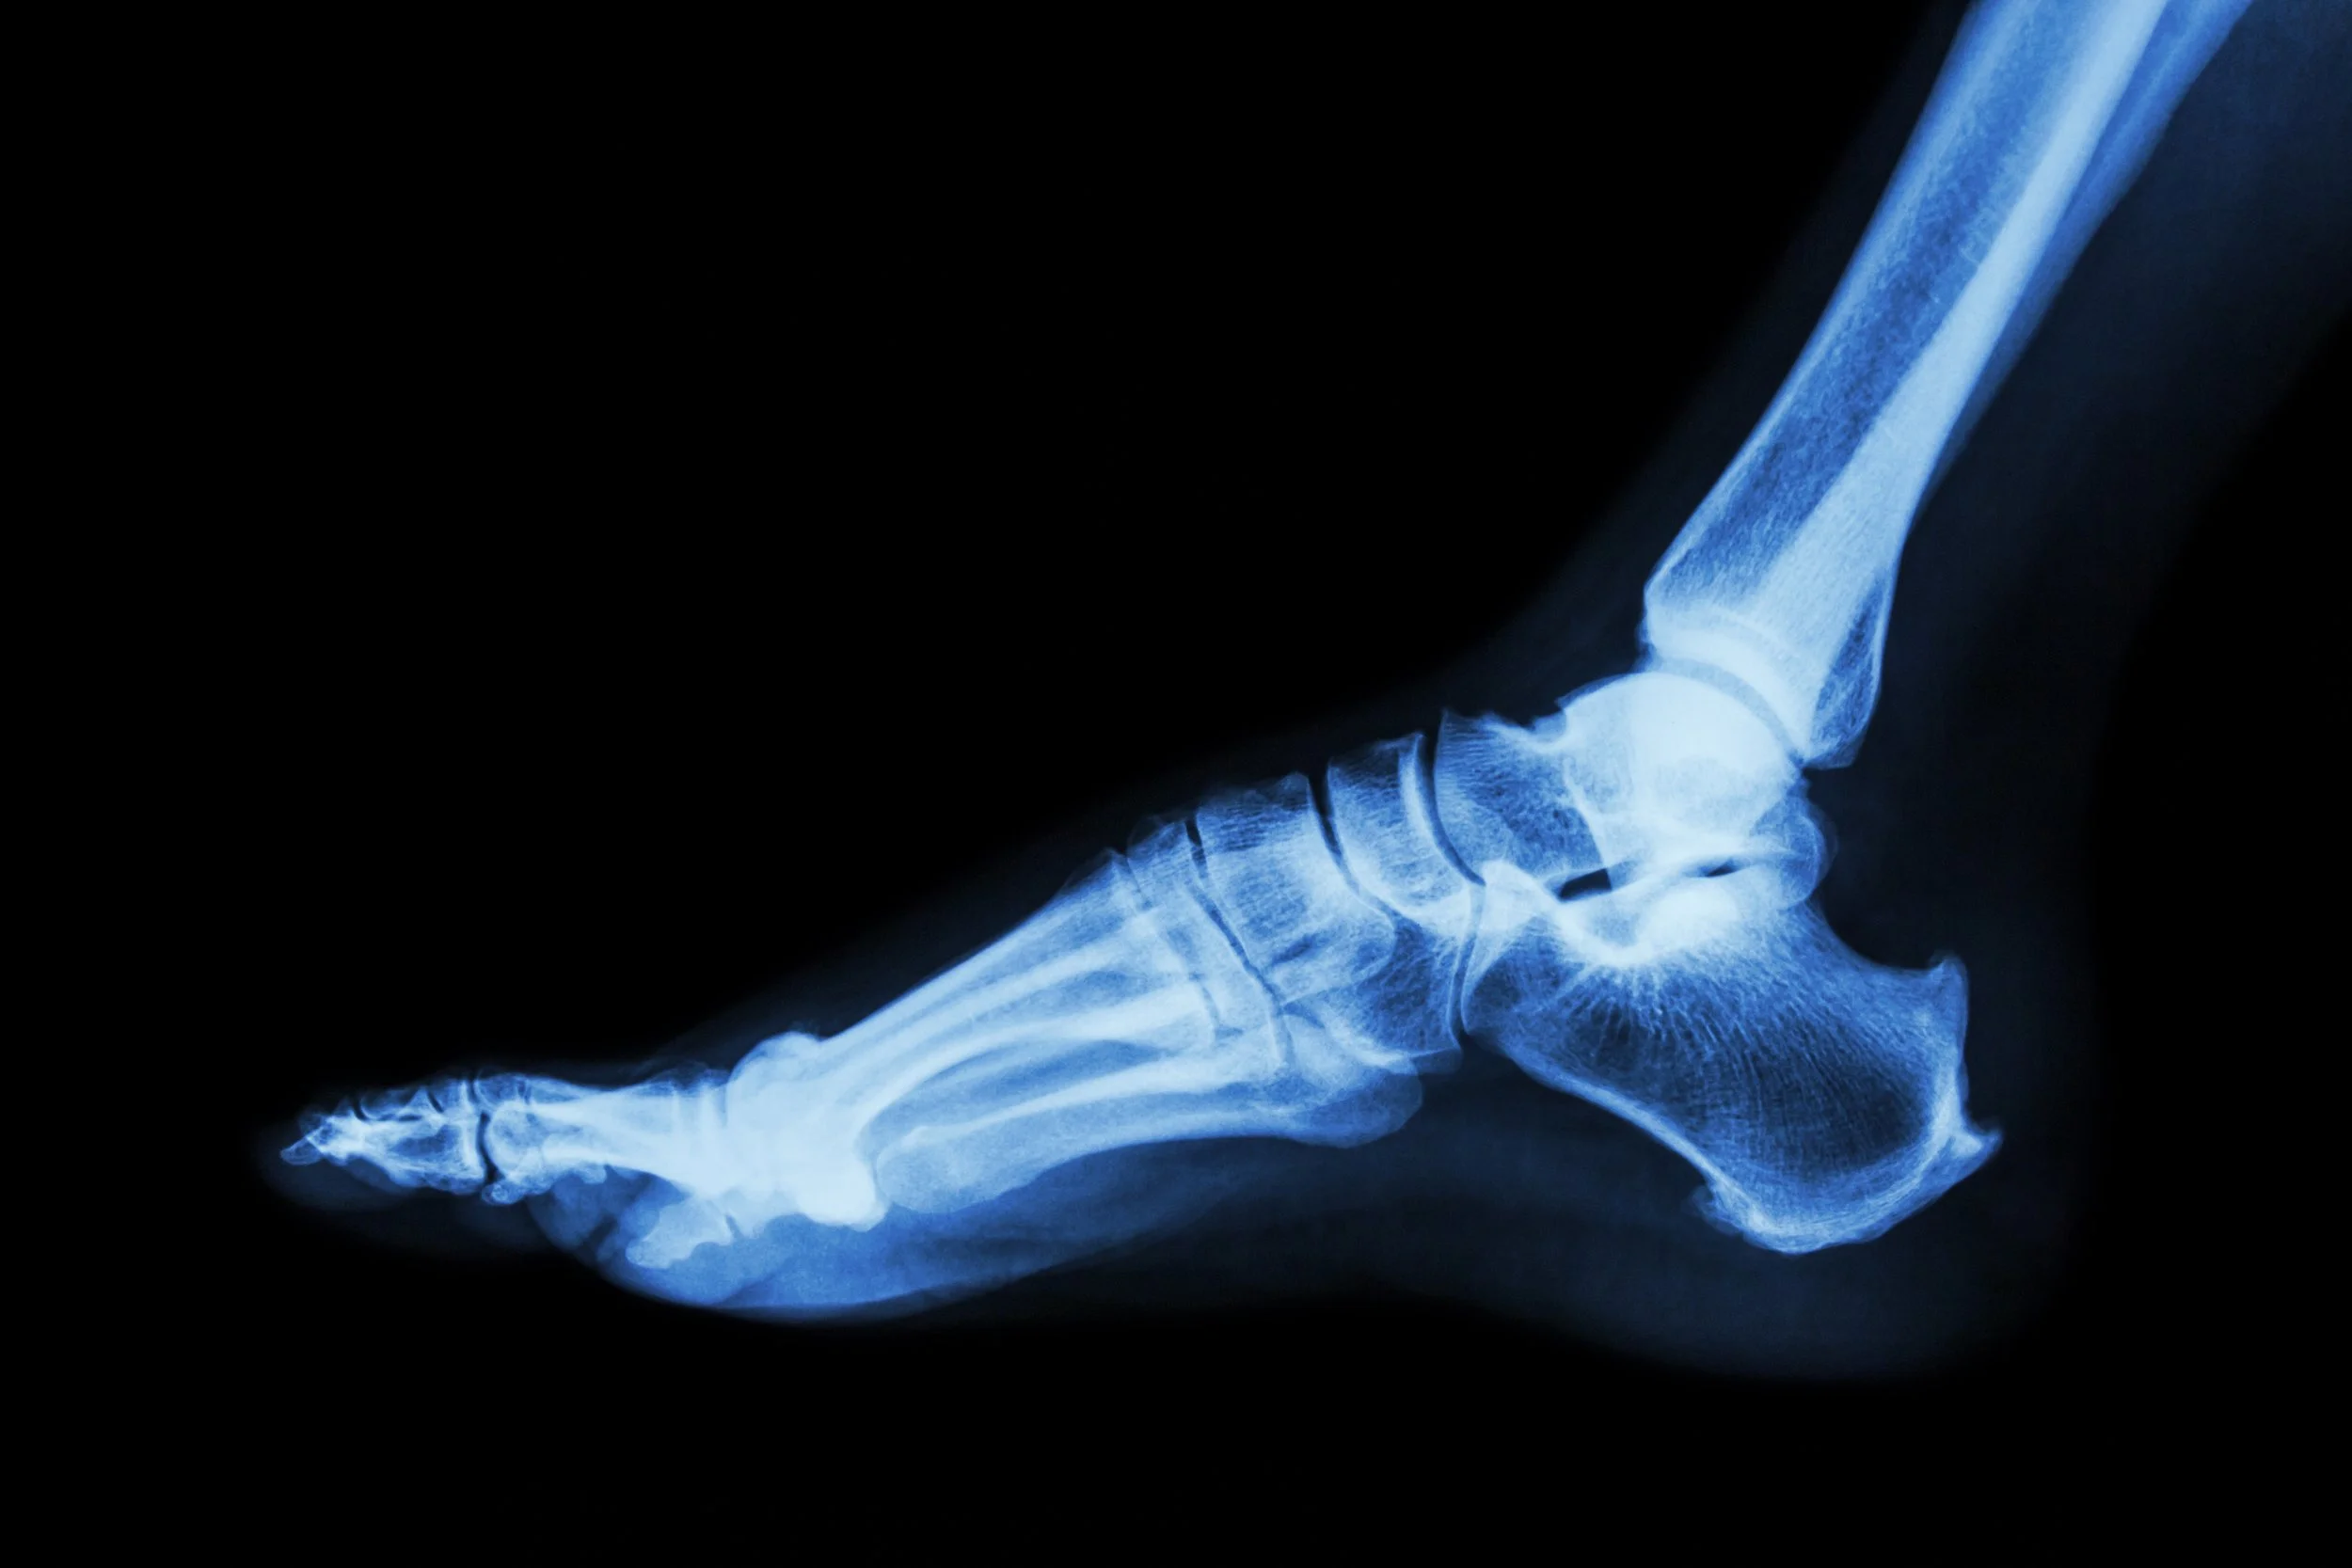

TSB Podiatry provides podiatry care in Prosper, Texas, treating foot pain, ankle injuries, heel pain, diabetic foot concerns, and other lower extremity conditions.

Dr. Trent Boehm provides focused care for the problems that most often disrupt daily life and activity, including heel pain, ankle pain, sports injuries, bunions, arthritis, ingrown toenails, diabetic foot concerns, and more.

Common reasons patients visit TSB Podiatry include:

Heel pain and plantar fasciitis

Ankle pain, instability, and sprains

Sports-related foot and ankle injuries

Bunions, hammertoes, and structural deformities

Joint pain and arthritis

Diabetic foot care, wound care, and infections